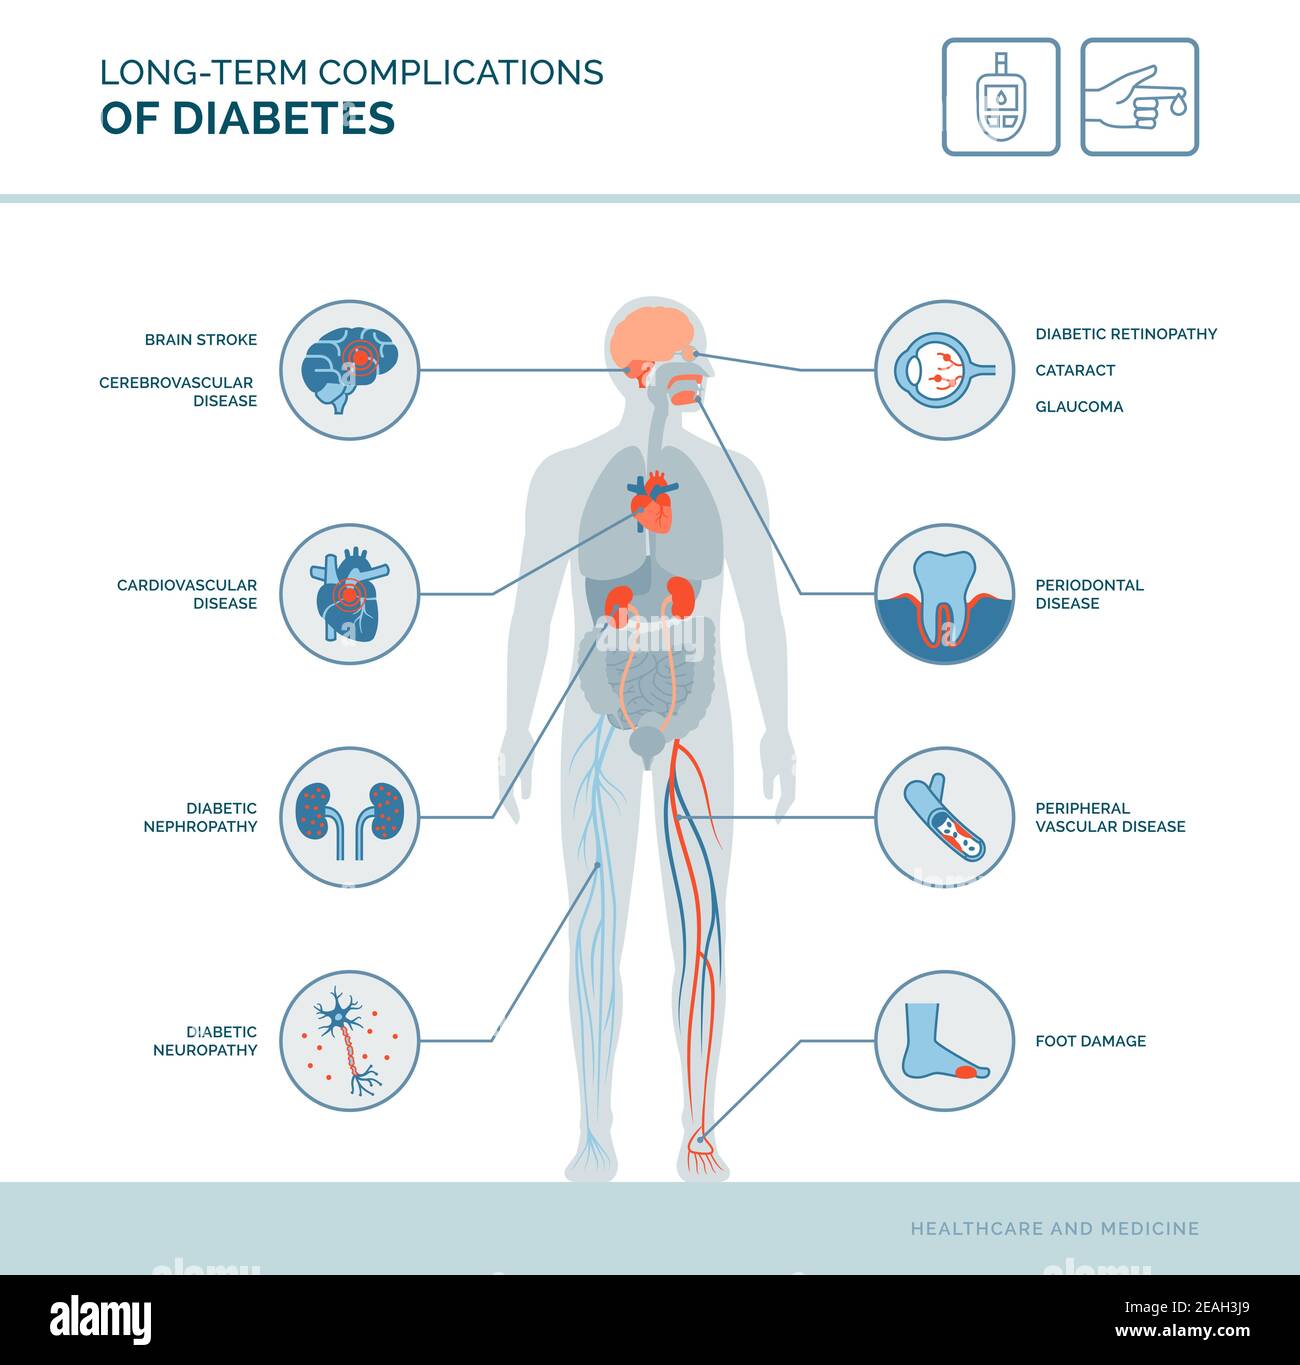

Long-term complications of diabetes medical infographic: diabetes effects on the body Stock Vectorhttps://www.alamy.com/image-license-details/?v=1https://www.alamy.com/long-term-complications-of-diabetes-medical-infographic-diabetes-effects-on-the-body-image402361073.html

Long-term complications of diabetes medical infographic: diabetes effects on the body Stock Vectorhttps://www.alamy.com/image-license-details/?v=1https://www.alamy.com/long-term-complications-of-diabetes-medical-infographic-diabetes-effects-on-the-body-image402361073.htmlRF2EAH3J9–Long-term complications of diabetes medical infographic: diabetes effects on the body